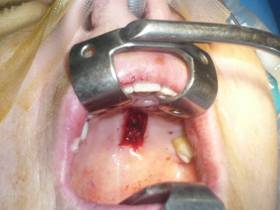

In mullerectomy stitches are not necessary and access is internal.

| Hard palate graft | |